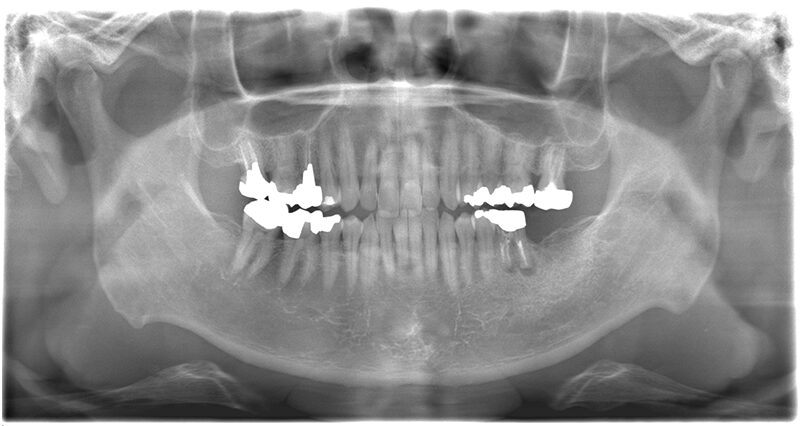

レントゲン、口腔内写真

- パノラマレントゲン写真

左下奥歯は根の下に膿がたまってしまっているようです。

それが痛みの原因の可能性が高いですね。

そうですよね。この歯に関しては被せ物をとって根の治療を再度行い、抜歯が必要なのか、保存することができるのか確かめる必要があります。